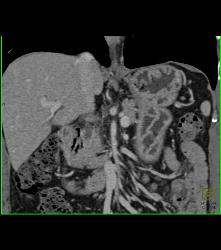

Thickened Gastric Folds